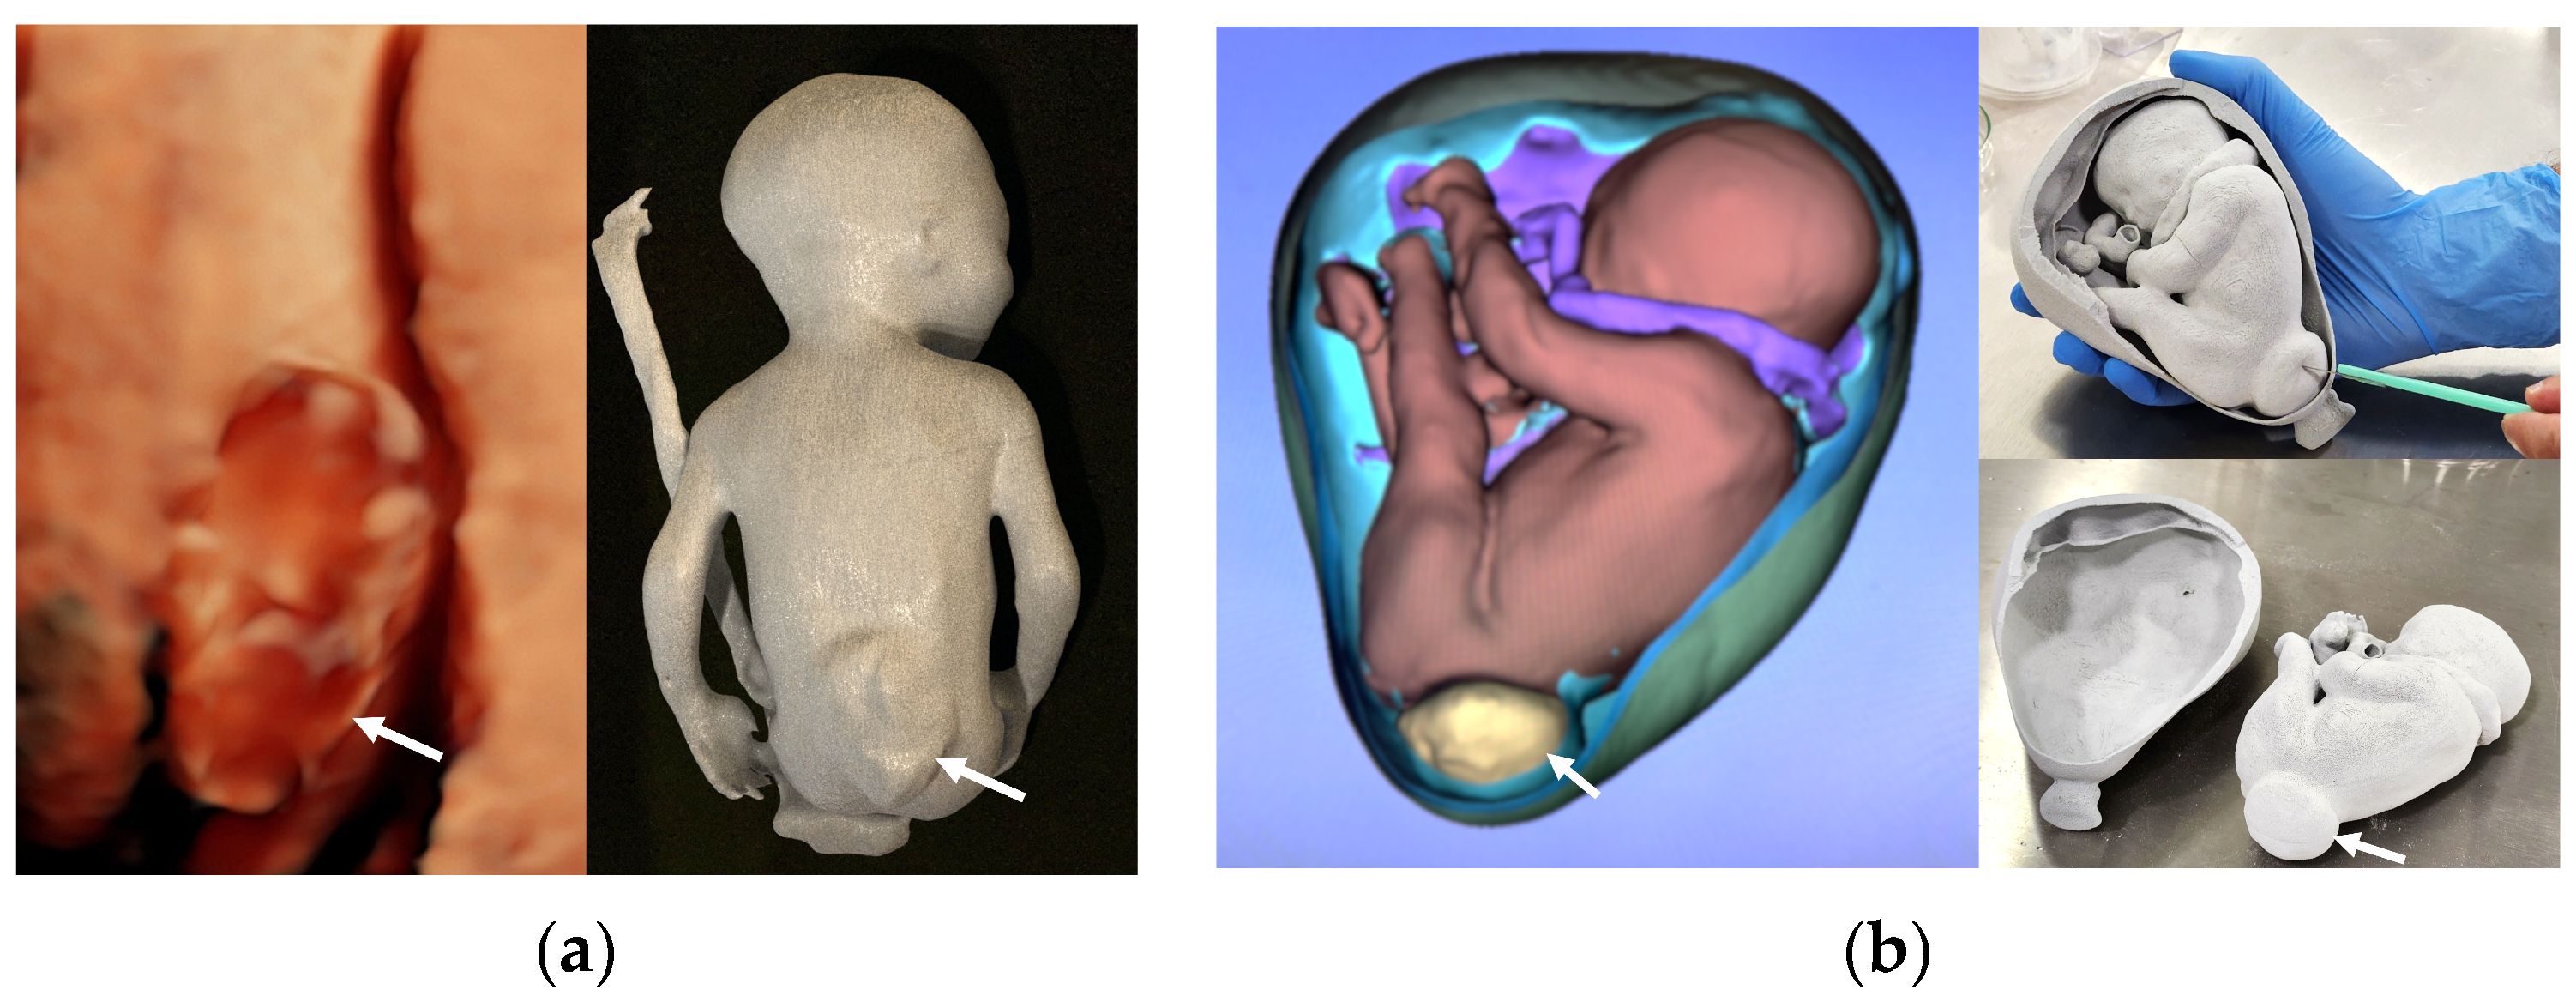

- Werner, H.; Rolo, L.C.; Araujo Júnior, E.; Dos Santos, J.R. Manufacturing models of fetal malformations built from 3-dimensional ultrasound, magnetic resonance imaging, and computed tomography scan data. Ultrasound Q. 2014, 30, 69–75. [Google Scholar] [CrossRef] [PubMed]

- Tutschek, B.; Blaas, H.K. A human embryo in the palm of your hand. Ultrasound Obstet. Gynecol. 2017, 50, 539–540. [Google Scholar] [CrossRef]